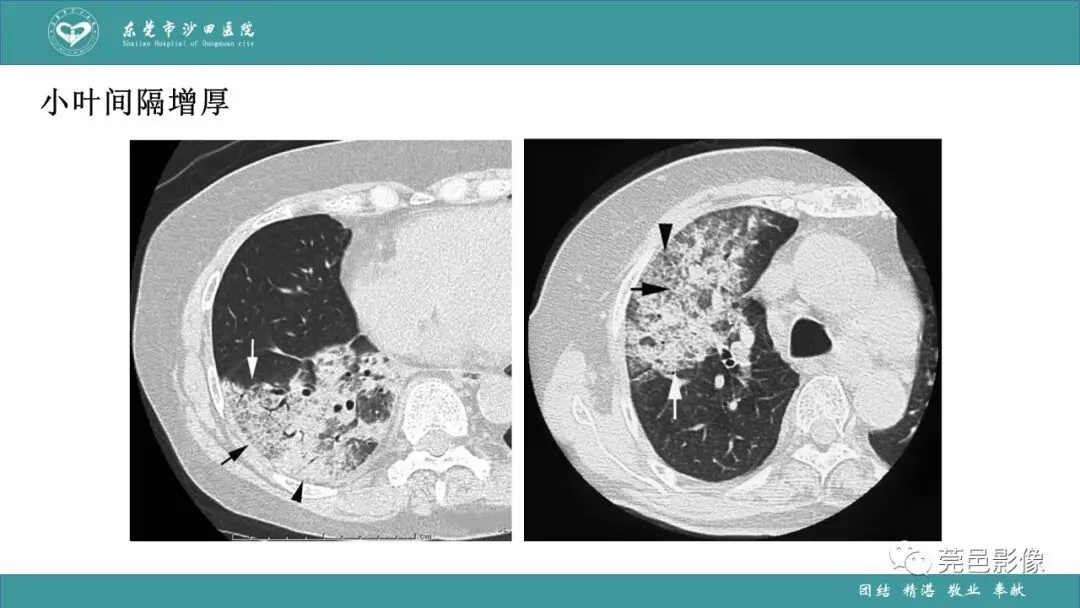

>课件 | 肺炎克雷伯杆菌肺炎影像学诊断与鉴别诊断

课件 | 肺炎克雷伯杆菌肺炎影像学诊断与鉴别诊断